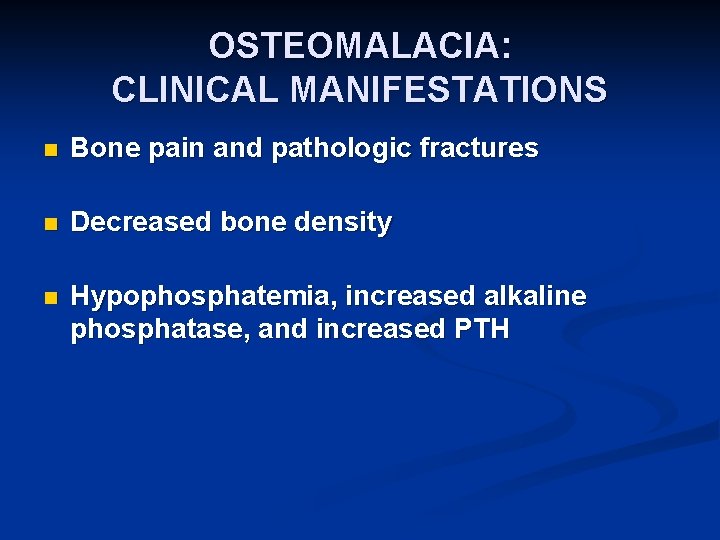

OSTEOMALACIA: CLINICAL MANIFESTATIONS n Bone pain and pathologic fractures n Decreased bone density n Hypophosphatemia, increased alkaline phosphatase, and increased PTH

OSTEOMALACIA: CLINICAL MANIFESTATIONS n Late hypocalcemia n Pseudofractures n In children, bowing of the legs and rachitic rosary, short stature